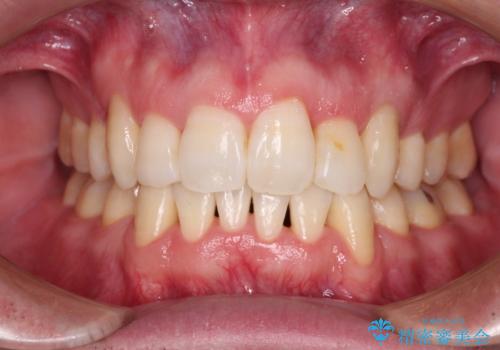

[インビザライン] 前歯のガタつき・すれ違い マウスピース矯正治療